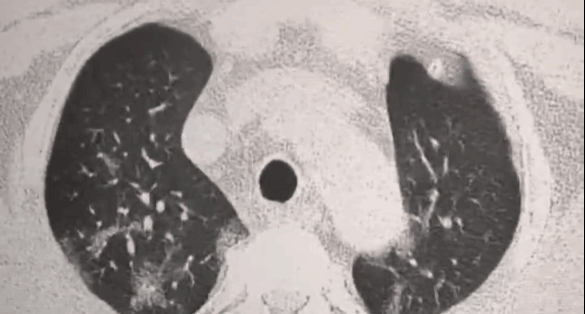

就会发展成肺结节,肺纤维化,甚至肺癌

严重危及生命

数据显示,肺癌是恶性肿瘤死亡的第一杀手

每年肺癌病人约有80万人

死于肺癌的病人大约是65万

一旦染上它,生存可能性非常小

受损的肺细胞会形成肺结节

进而引发肺部纤维化、甚至肺ai

医学上对肺结节没有特效药

一般只能手术切除

对肺部的伤害大,有副作用